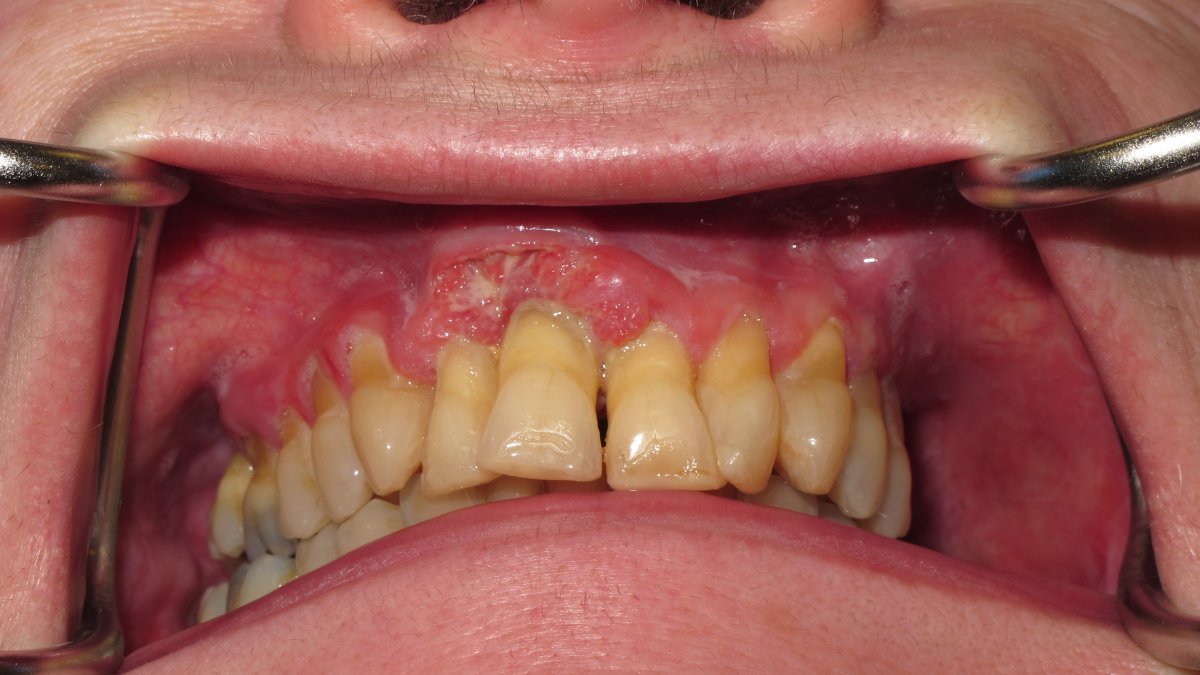

Gingival tumour